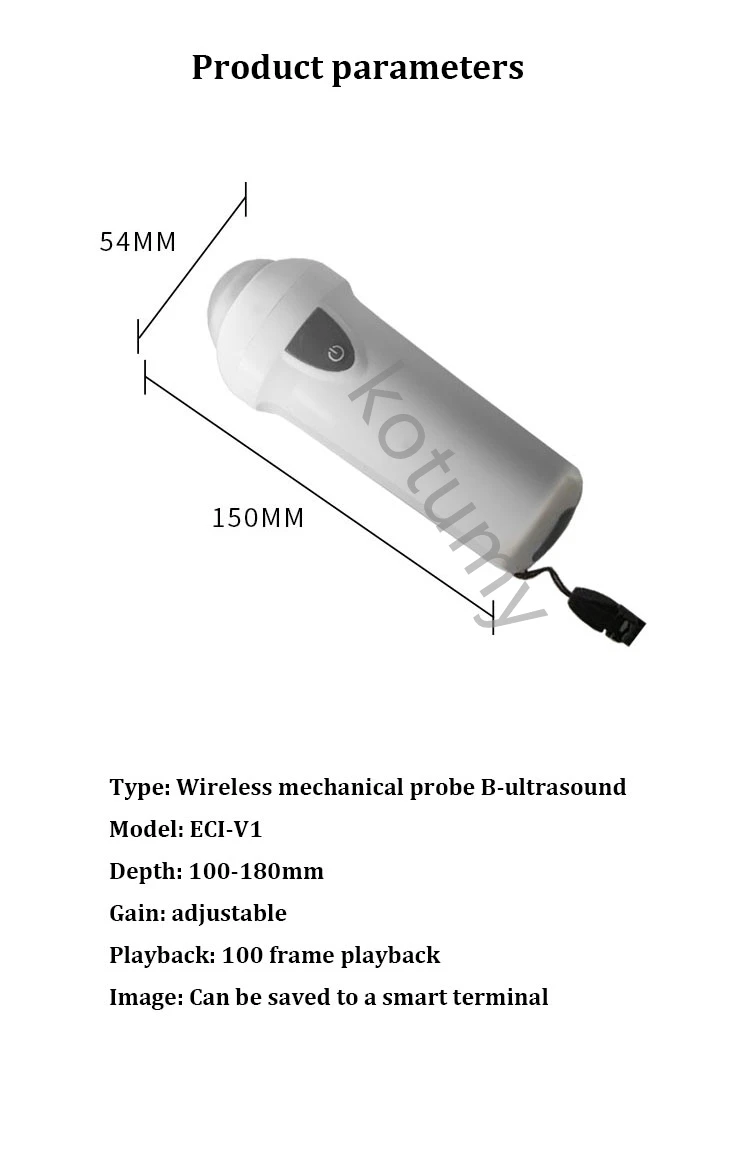

Tipo: Sonda mecânica sem fio B-ultra-som

Modelo: ECI-V1

Profundidade: 100-180mm

Ganho: ajustável

Reprodução: reprodução 100 quadros

Imagem: Pode ser salvo em um terminal inteligente